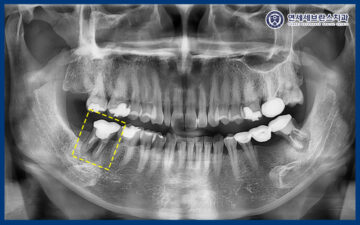

24.08.02

정밀한 상태 확인을 위해

파노라마 촬영을 진행하였습니다.

그 결과, 치조골 소실로 인해

크라운 내부 상태가 좋지 않을 가능성이

높게 확인되었습니다.

환자분께서는 치아를 살려

사용해보기를 원하셔서,

기존 크라운을 제거한 뒤

다시 평가하기로 하였습니다.

다만 뿌리가 이미 파절되어 있을 가능성도 있어,

보존 치료를 하더라도

사용 기간이 길지 않을 수 있음을

안내드렸습니다.